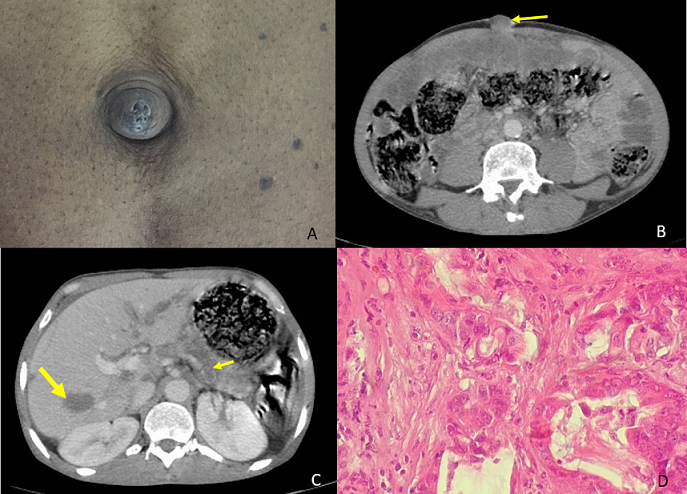

Sister Mary Joseph's nodule is a metastatic of a primary cancer, usually adenocarcinoma and associated with poor prognosis. Here we report the case of a 48-year-old man, admitted to the hospital with six months history of epigastric pain without vomiting or externalized hemorrhage and without transit disorders in a context of alteration of the general state with weight loss. Clinical examination showed epigastric sensitivity with a painful umbilical nodule, firm and irregular (A). Laboratory tests revealed a cholestasis. His computed tomography (CT) of the abdomen showed a mass lesion at the tail of the pancreas measuring 45 mm enclosing the splenic artery with secondary ganglionic, hepatic, bone and peritoneal localization (B, C). The umbilical lesion biopsies revealed metastasis of the pancreatic adenocarcinoma (D). The patient received palliative chemotherapy.